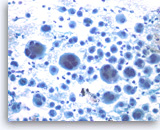

Non-Hodgkin B-cell lymphoma,

Pancreas FNA, Direct Smear.

The aspirates show dispersed single intermediate to large atypical lymphocytes.

20X

Non-Hodgkin B-cell lymphoma,

Pancreas FNA, Direct Smear.

The aspirates show dispersed single intermediate to large atypical lymphocytes.

20X